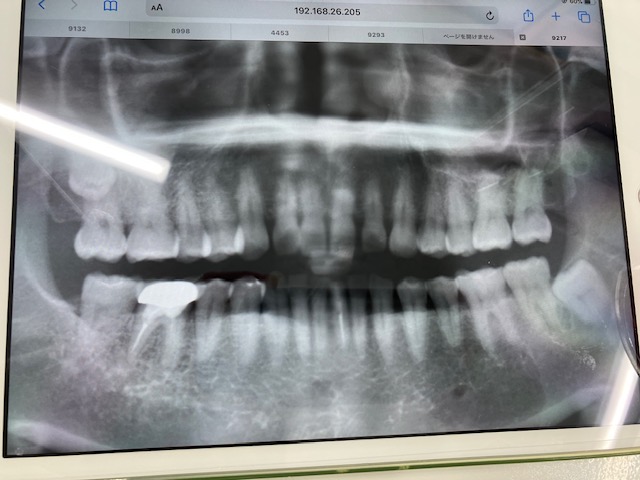

画像2:2025年1月に撮影したもの

画像2

船橋歯科医院(岡山市北区)の船橋です。

今回個人的には3度目の根管治療は必要だと思います。

それはデンタルには写っていないものがパノラマには写っているように思えるからです。

つい先日、かかりつけ医で歯のクリーニングをした時にレントゲン写真を撮ってきたのですが主治医からは根尖病変は無いようにみえると言われました。

(こちらに掲載した画像は 2025年1月のもの)

でも、柴田先生から

【今回個人的には3度目の根管治療は必要だと思います。

それはデンタルには写っていないものがパノラマには写っているように思えるからです。】